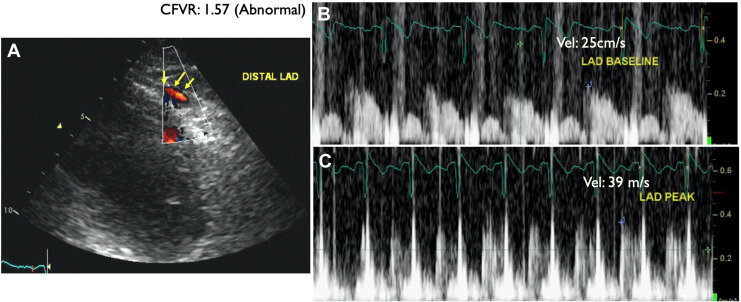

Step D: CFVR

• Assessment: Coronary flow velocity reserve of mid-distal LAD

• Positivity: CFVR < 2

• Success rate of 88% in obtaining CFVR on LAD (3000/3410)

• 80% with exercise (bike) and 81% with dobutamine

•  Acquisition and Interpretation in < 4 minutes

• Assesses both epicardial CAD and coronary microcirculation

• Dopplers obtained and reviewed offline

• *Note: Stress Echo 2030 protocol, pharm SE or if exercise, then given adenosine bolus at end of recovery to assess CFVR

• Acquisition: modified low parasternal and apical views

• Studies agree, onerous, but with training it is possible

• Angina

• No WMA

• CFVR < 2

• Dx:  chronic microvascular dysfunction